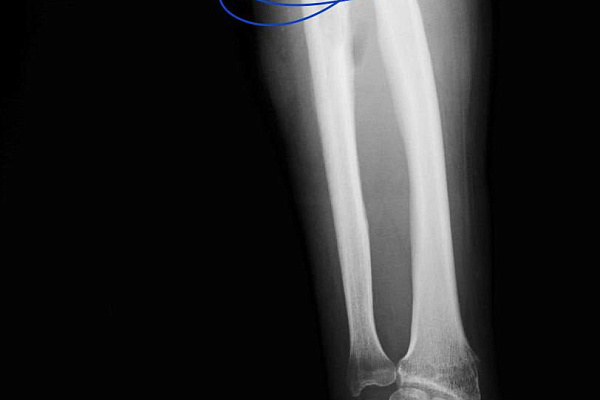

-В первую очередь нам необходимо было справиться с инфекцией. При свищевом остеомиелите ждать результата от обычной антибактериальной терапии бессмысленно. Воспалительный процесс разрушил кость на участке длиной 8 сантиметров. Этот фрагмент подлежал удалению в пределах здоровых тканей. На его место установили спейсер из антибиотика и костного цемента. Мы изготовили его самостоятельно в условиях операционной, по собственной технологии и индивидуальным размерам. Имплантат выполнял двойную задачу. Во-первых, это источник антибиотика в непосредственном очаге заражения. Во-вторых,- механическая поддержка для кости за счёт своей армирующей функции, - объясняет Сергей Глиняный.

Благодаря профессионализму и смекалке врачей, ещё на этапе лечения остеомиелита пациент впервые вновь начал двигать рукой и приступил к её разработке. Спейсер, зафиксированный на участке недостающего костного фрагмента, создавал эффект целостности кости на протяжении всех двух месяцев антибактериальной терапии. Однако самый ответственный этап был впереди.